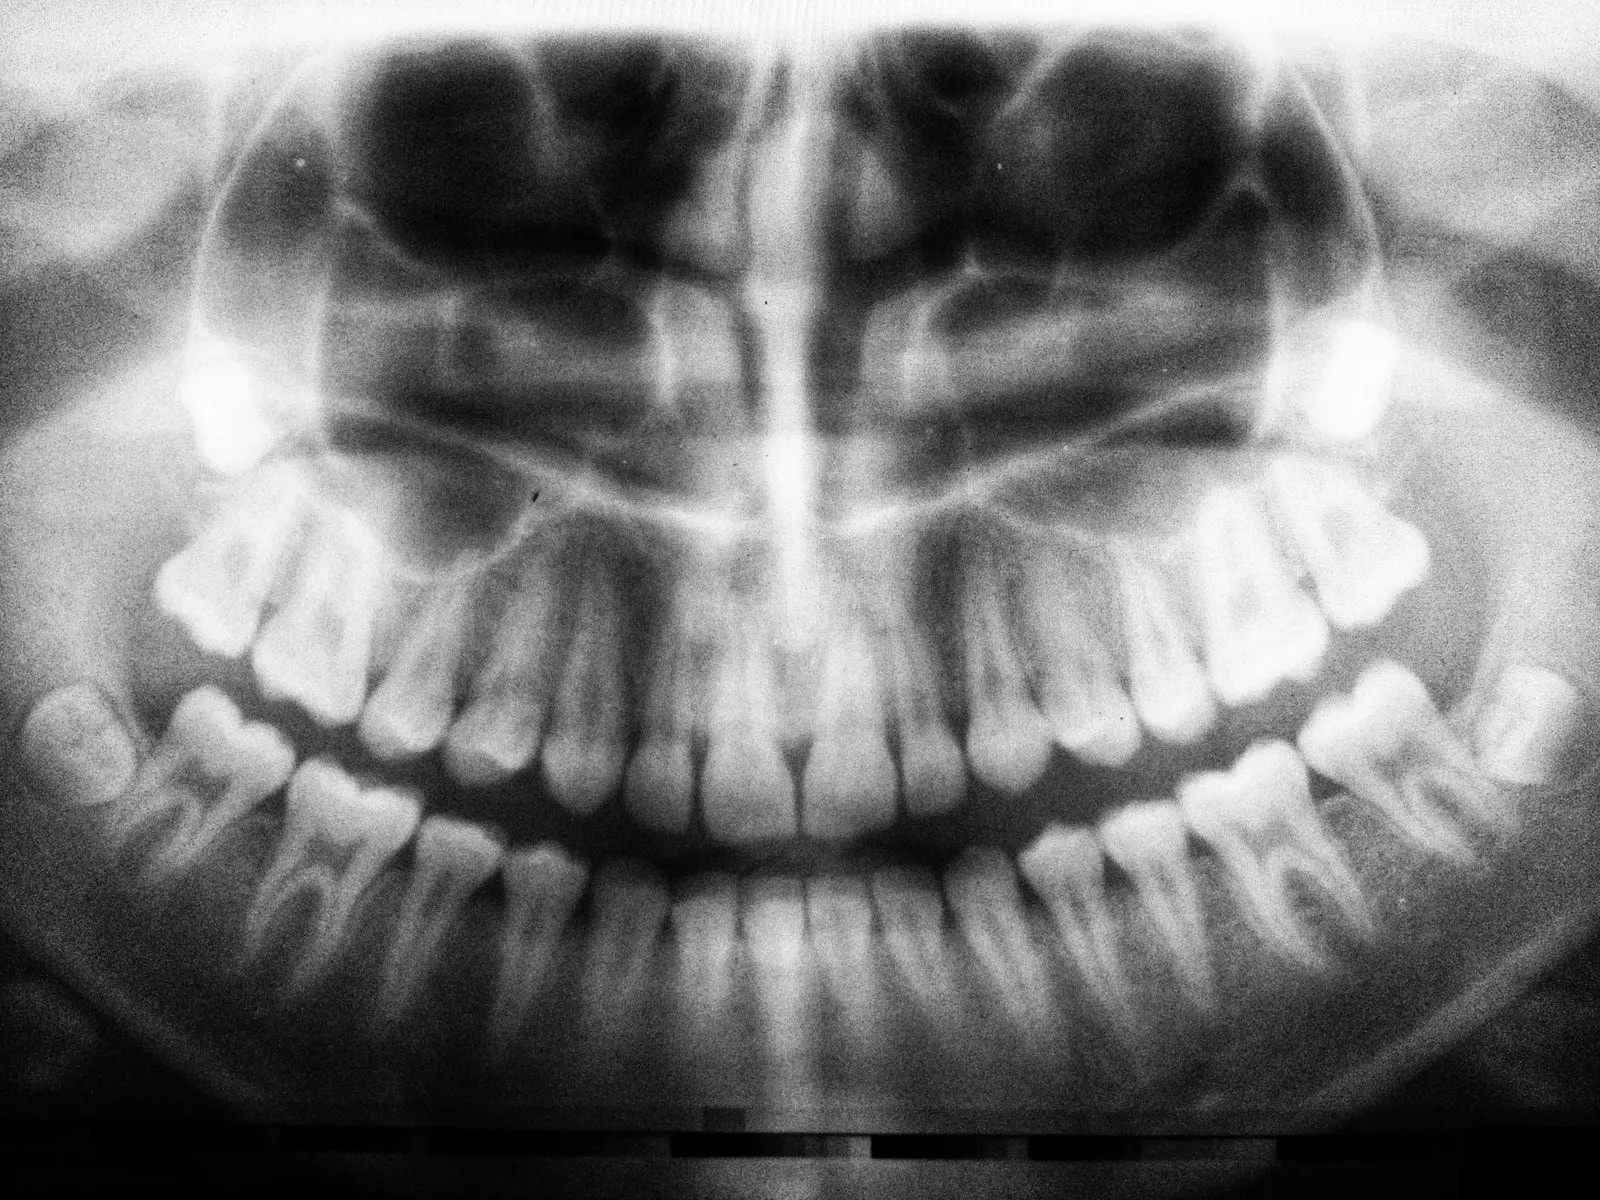

2) Artificial intelligence can also assist dental professionals in diagnosing diseases using images taken from X-rays and other medical imaging techniques. This would allow them to identify problems before they become serious.

The use of artificial intelligence has been proposed as an alternative method for detecting caries lesions on teeth. The system uses image processing techniques to identify tooth surfaces with white spots indicative of early stages of decay. It then compares these images against previous examinations to determine whether any new areas have developed since the last review. If so, it alerts the dentist, who may decide to perform the further treatment.

Finally, AI can also save money by helping us identify cost-effective solutions to common issues. For example, we could use AI to predict the likelihood of developing caries. Then, rather than spending hours manually reviewing x-rays, we could simply send them directly to specialists who would then make recommendations regarding further testing and possible interventions. This approach not only saves time but reduces unnecessary radiation exposure.